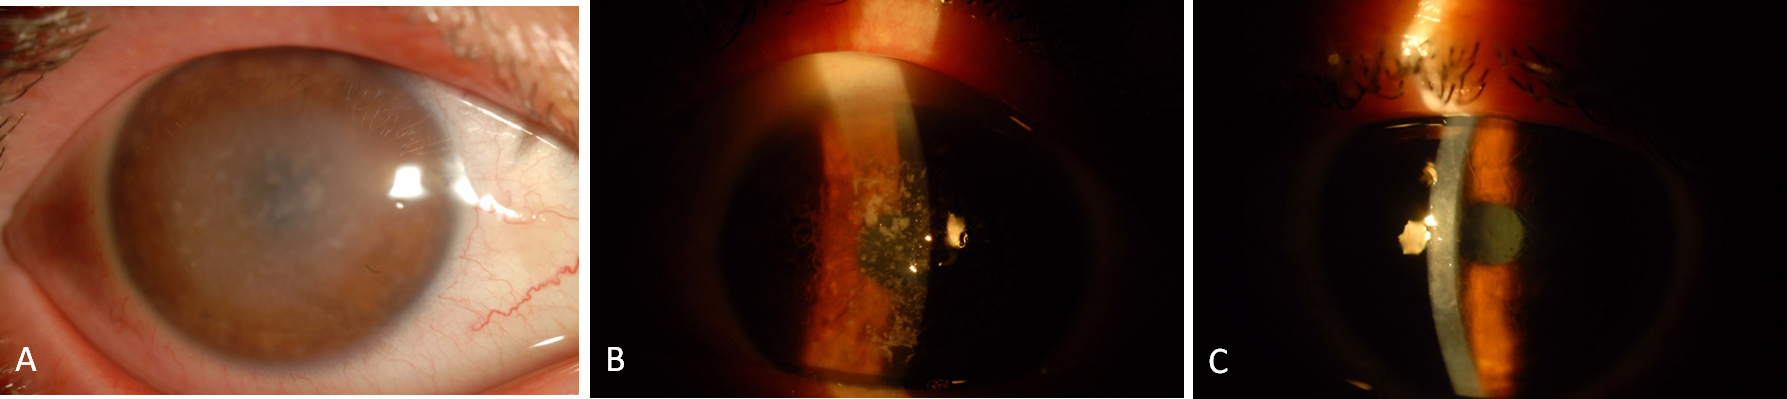

Figure 1.

AS photographs of patients.

A

: Macular corneal dystrophy patient (patient 9).

B

: Patient with granular corneal dystrophy type 1 (patient 5).

C

: Patient with lattice corneal dystrophy type 1 (patient 2).